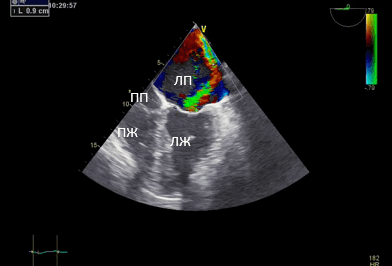

Данные интаоперационной 3D ЧП ЭхоКГ: Митральный клапан: ФК 44 мм, створки уплотнены, расщепление передней створки от свободного края до фиброзного кольца в сегменте А 2, движение створок разнонаправленное. Градиент давления максимальный — 6,2 мм рт.ст., средний 2,1 мм рт.ст. Регургитация выраженная: vena contracta - 0,9 см, площадь потока регургитации — 11,4 см², в непрерывноволновом допплеровском режиме плотный поток регургитации, радиус PISA — 1,0 см. Регургитация — эксцентричная, по боковой стенке ЛП.

Рис. 2. Чреспищеводная эхокардиография. Среднепищеводный доступ. Четырёхкамерная позиция. (ПП — правое предсердие). Площадь потока регургитации — 11,4 см².

Рис. 3. Чреспищеводная эхокардиография. Среднепищеводный доступ. Четырёхкамерная позиция. Vena contracta 0,9 см.